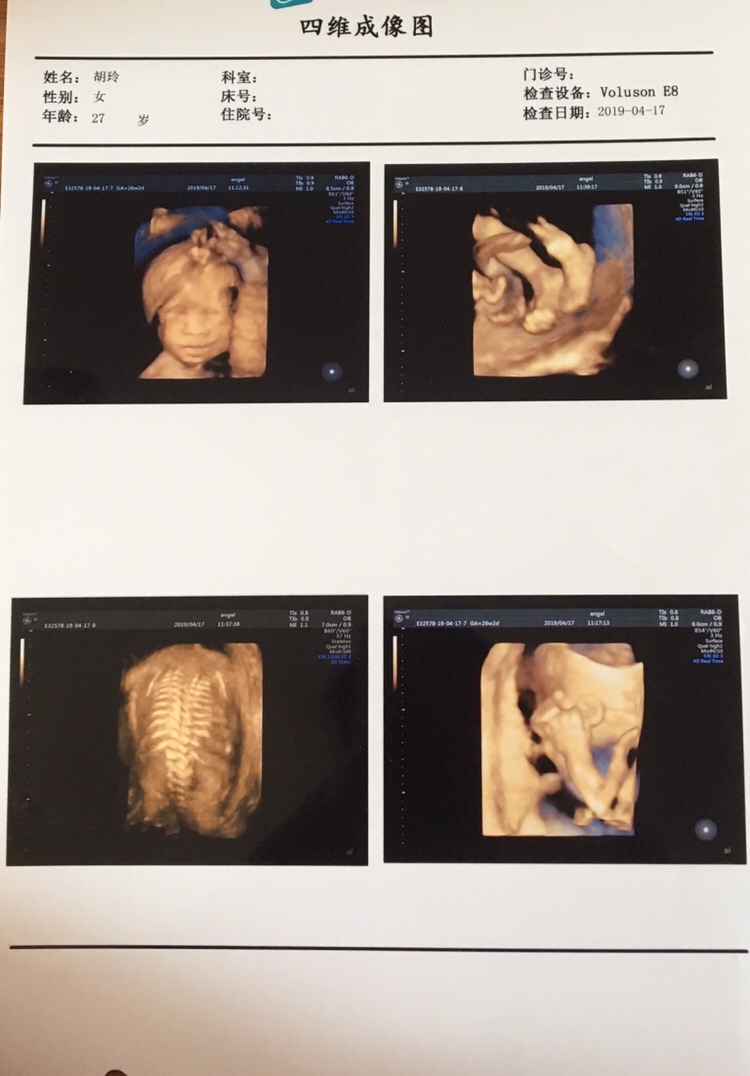

几周做的B超,

HYGJCvtA[帖主]:23+4做的思维,人家说是女宝